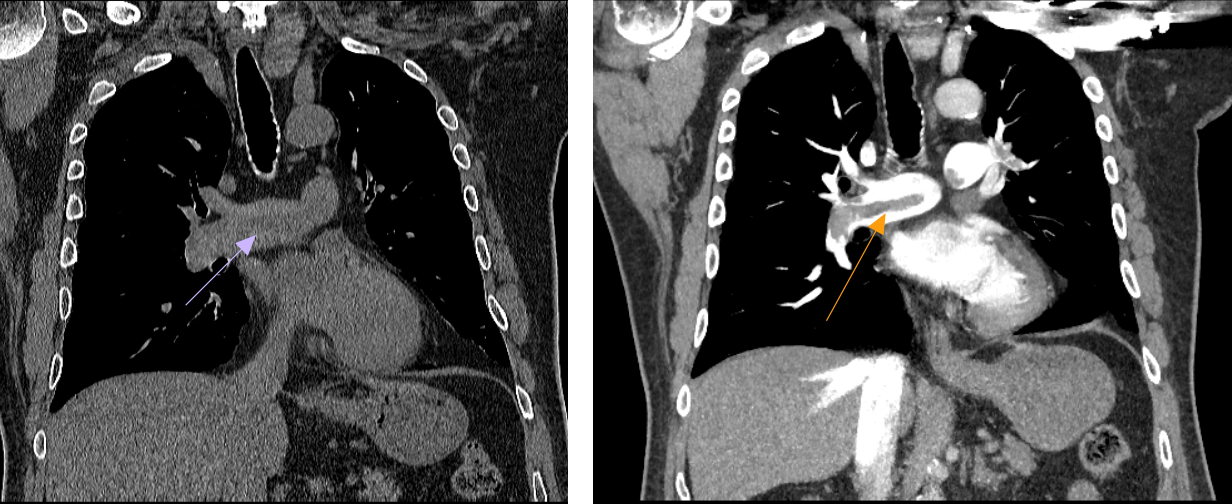

A day later, a non-contrast CT was ordered to evaluate the parenchymal lung disease as the source of dyspnea. Findings on imaging, as shown below in Figure 1, indicate a saddle pulmonary embolism. The subsequent CTA (Figures 1&2) showed the thrombus and contrast-enhanced imaging. In Figure 1, the attenuation differences between the clot and flowing blood in the pulmonary artery are seen. In Figure 2, the red arrow points to the saddle pulmonary embolism straddling the right and left pulmonary arteries.

Figure 1 Left: Non-contrast Coronal CT. The purple arrow points to the saddle pulmonary embolism that is straddling the right and left pulmonary arteries. The attenuation differences between the clot and flowing blood in the pulmonary artery are seen here; Right: Coronal CTA. The orange arrow points to the saddle pulmonary embolism that is straddling the right and left pulmonary arteries.